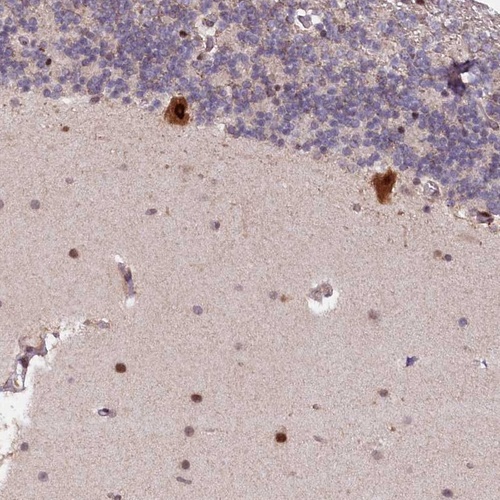

Immunohistochemical staining of human cerebellum shows strong cytoplasmic and nuclear positivity in Purkinje cells.